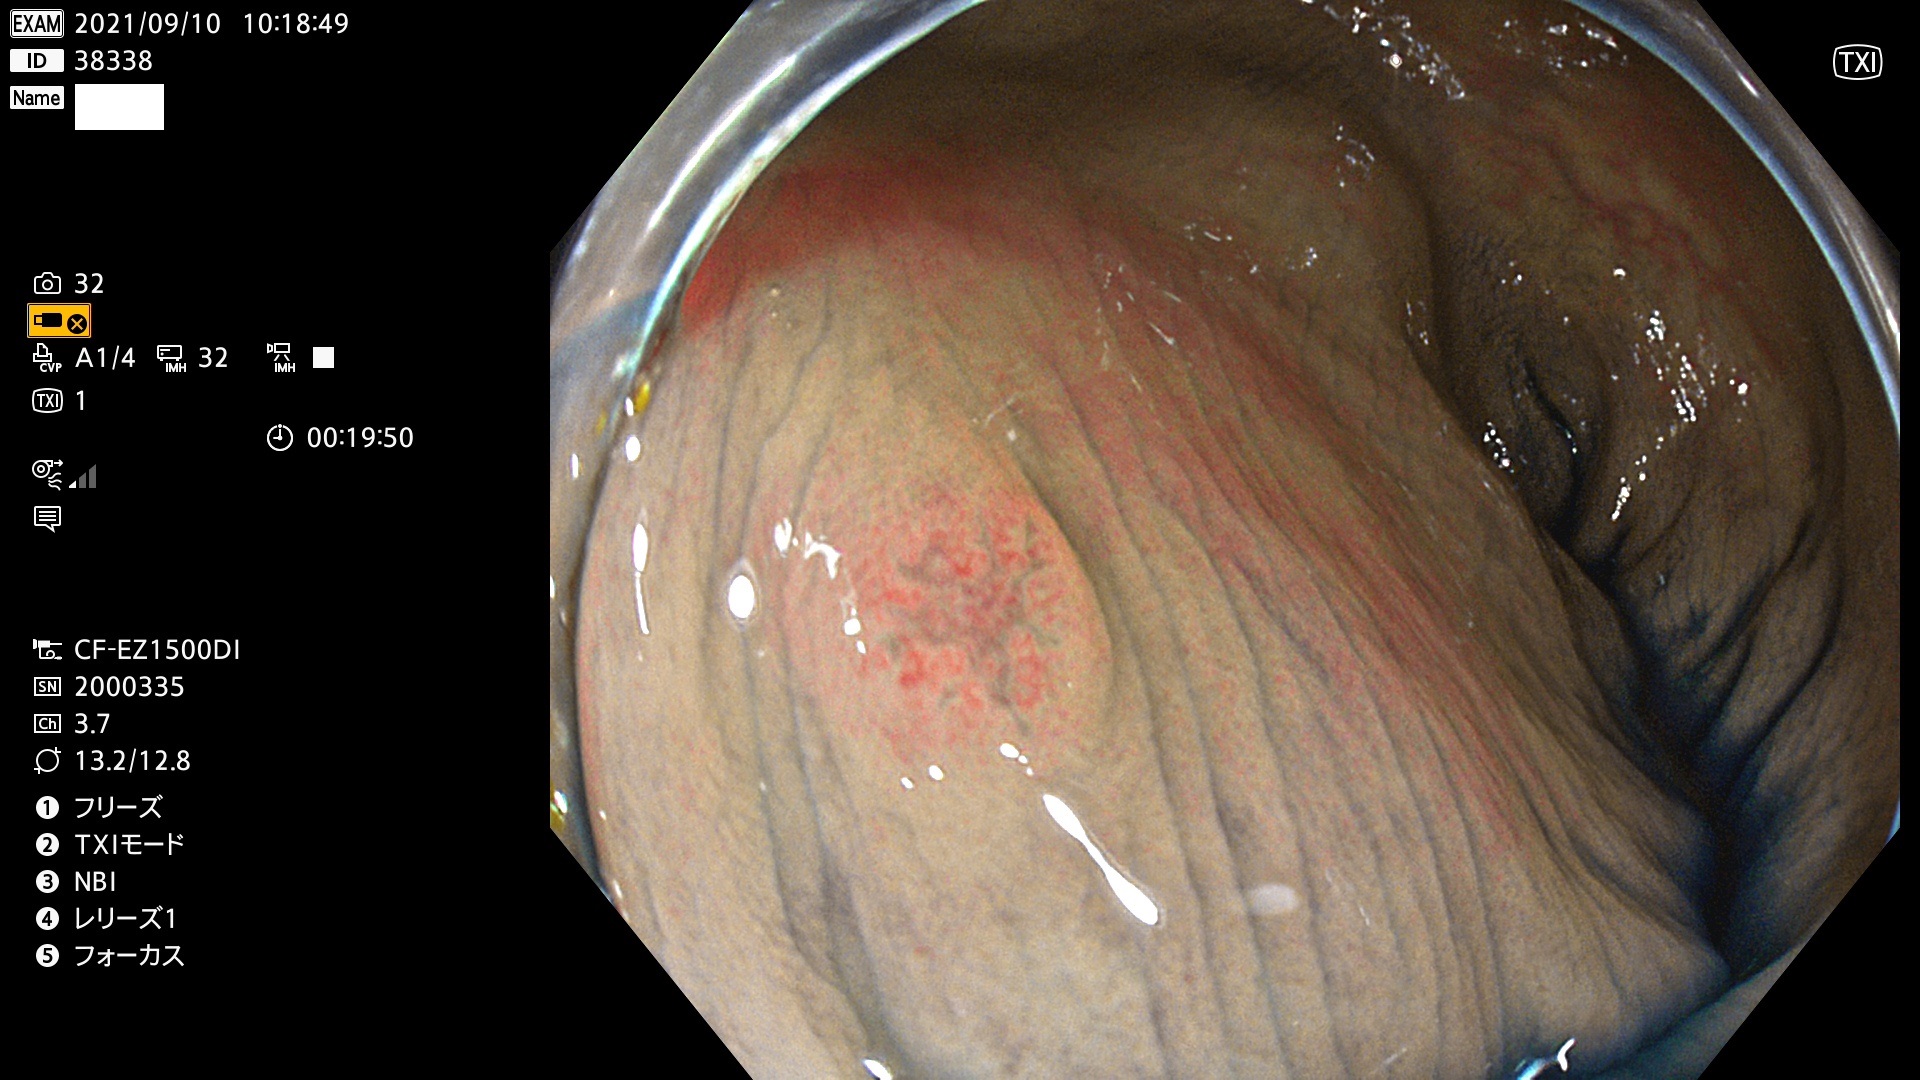

38300 38301 38302 38303 38304 38306 38307 38308 38309 38310 38311 38312 38313 38314 38315 38316 38317 38319 38321 38322 38323 38324 38325 38327 38331 38332 38333 38334 38337 38338 38339 38340 38341 38343 38346 38348 38349 38350 38351 38352 38353 38354 38355 38358 38359 38360 38361 38362 38363 38365 38366(SSAP) 38368 38369 38370 38371(SSAP) 38372 38374 38375 38376 38377 38378 38380 38381 38382 38383 38384 38385 38386 38388 38389 38391(SSAP) 38395 38397 38399

発見困難で危険性の高い平坦型病変(上記100名より抽出)